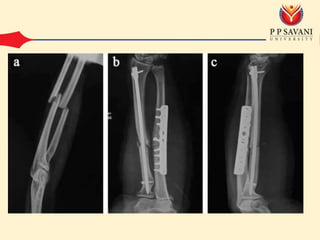

• ORIF

– Compression plating and intra medullary nailing is

preferred method

• ORIF – Radiusand ulna should be approached through separation incisions to avoid cross union – Compression plating and intra medullary nailing is preferred method – Bone grafting should be used in fracture older then 3 weeks – Limb should be mobilized depending upon rigidity of the fixation – External fixation is used in some compound fracture